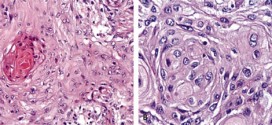

CÁNCER EPIDERMOIDE DE ESÓFAGO

El cáncer epidermoide de esófago. Tumor maligno en general y especialmente formado por células epiteliales. El cáncer epidermoide de esófago es una enfermedad por la que se forman células malignas (cancerosas) en los tejidos del esófago. El esófago es el tubo hueco, muscular que transporta los alimentos y los líquidos desde la garganta al estómago. La pared del esófago comprende …